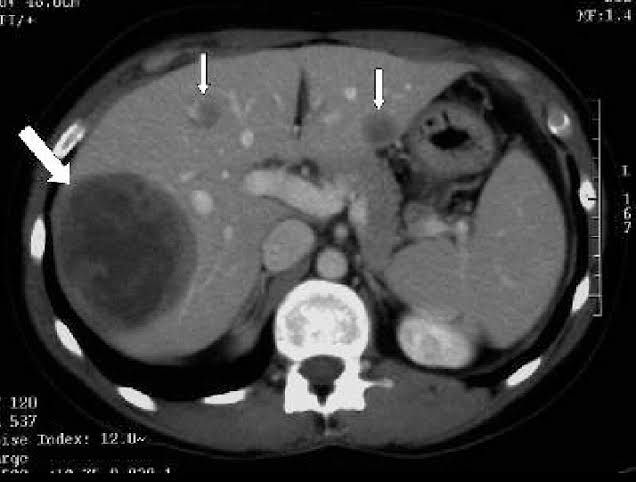

Hypodense splenic lesions are frequently encountered on abdominal CT images. Although most hypodense lesions of the spleen can be considered benign, some findings and clinical conditions warrant closer attention to the lesion.